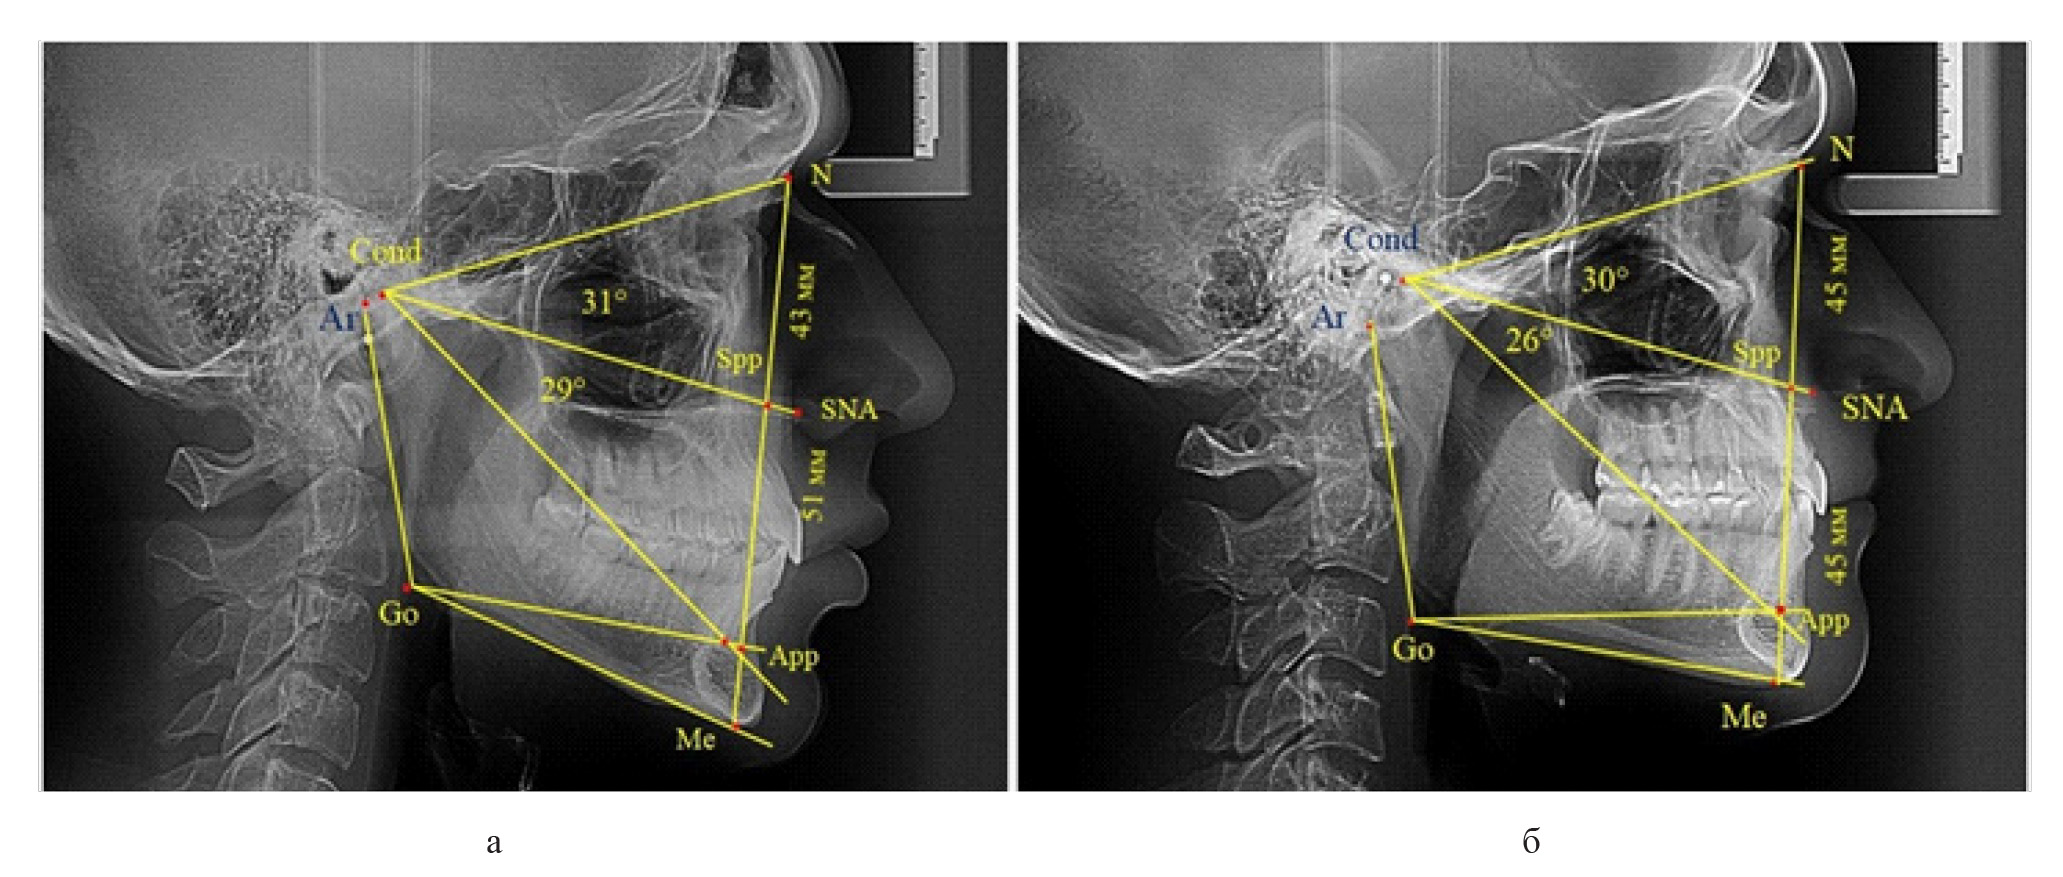

Вертикальная линия передней высоты лица (N-Me), после ее пересечения с линией Cond-SNA, определяла положение точки Spp, при этом вертикаль N-Spp использовалась в качестве оценки высоты назального отдела лица. Продолжение линии Go-Api до пересечения с линией N-Me позволяла определить положение конструктивной точки Арр и оценить линейные размеры гнатической части лица по величине вертикали Spp-Арр (рис. 1).

Рис. 1. Методы оценки основных параметров ТРГ для определения вертикальных размеров лицевого отдела головы

Рис. 4. Варианты ТРГ с укороченными размерами носового отдела и оптимальными (а) и укороченными (б) размерами гнатической части

Среди пациентов с аномалиями челюстно-лицевой области в вертикальном направлении у 24 человек определялась глубокая резцовая окклюзия/дизокклюзия (рис. 5).

Рис. 5. Варианты ТРГ с оптимальными размерами носового отдела и оптимальными (а) и укороченными (б) размерами гнатической части лица

При этом только в двух случаях [(8,33 ± 5,64) %], параметры носового и гнатического отдела соответствовали норме. У 9 человек [(37,59 ± 9,88) %], при оптимальных параметрах назального отдела отмечалось уменьшение высоты гнатического отдела, вплоть до патологических показателей.

У людей с глубокой резцовой окклюзией нередко отмечалось изменение параметров носового отдела лица. Так, в 7 случаях было выявлено снижение параметров как носового, так и гнатического отделов лица. У 5 человек [(20,83 ± 8,28) %], отмечалось уменьшение носового отдела лица при оптимальных параметрах гнатического отдела.

В одном случае [(4,17 ± 4,08) %], определялось патологическое увеличение назального отдела лица при уменьшении гнатической его части. Некоторые варианты ТРГ пациентов с глубокой резцовой окклюзией представлены на рис. 6.

Рис. 6. Варианты ТРГ с уменьшенными размерами носового отдела и оптимальными (а) и укороченными (б) размерами гнатической части лица при глубокой резцовой окклюзии